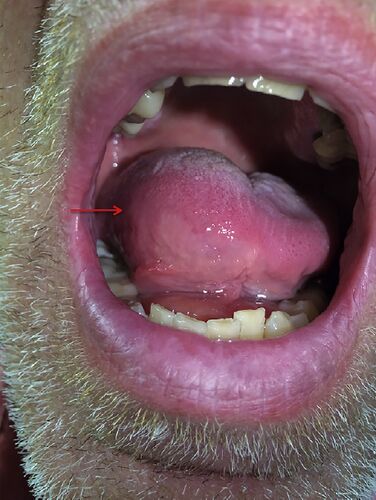

症例3:2日間持続する嚥下時痛を訴える55歳男性(Ann Emerg Med. 2017 Apr;69(4):514-528.)

病歴/身体所見 ・55歳男性 ・2日間持続する、咽頭右側の重度で鋭い疼痛 ・疼痛のため嚥下ができない ・発熱//悪寒/呼吸困難/最近の歯科処置/口腔外傷歴なし ・バイタルサインに異常なし ・免疫不全の病歴なし ・舌右側の著明な腫脹と圧痛を認めた 検査 ・造…